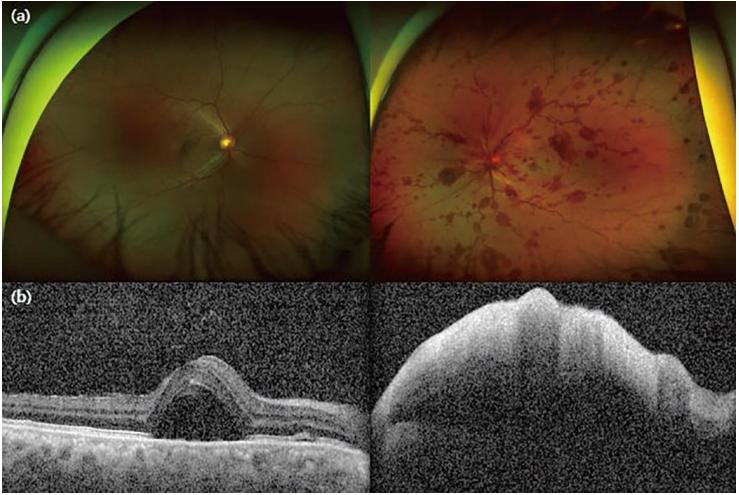

一天后,患者主诉左眼突然出现无痛性视力丧失。矫正后的右眼视力为0.7,眼底镜检查显示视网膜血管系统相对正常,中央凹周围区域有浆液性视网膜脱离。左眼眼底镜检查显示视盘肿胀,伴有乳头周围出血、弥漫性视网膜下出血、四个象限的视网膜静脉扩张和弯曲,以及黄斑周围变白。OCT显示右眼视网膜下积液增多,左眼神经感觉视网膜层弥漫性增厚和高反射,伴有明显的后阴影(图1a,b)。此外,左眼荧光素血管造影术显示脉络膜填充延迟和显著的动脉填充缺陷,以及右眼视网膜下空间的染料泄漏和聚集点。

图1. 眼底镜和光学相干断层扫描结果